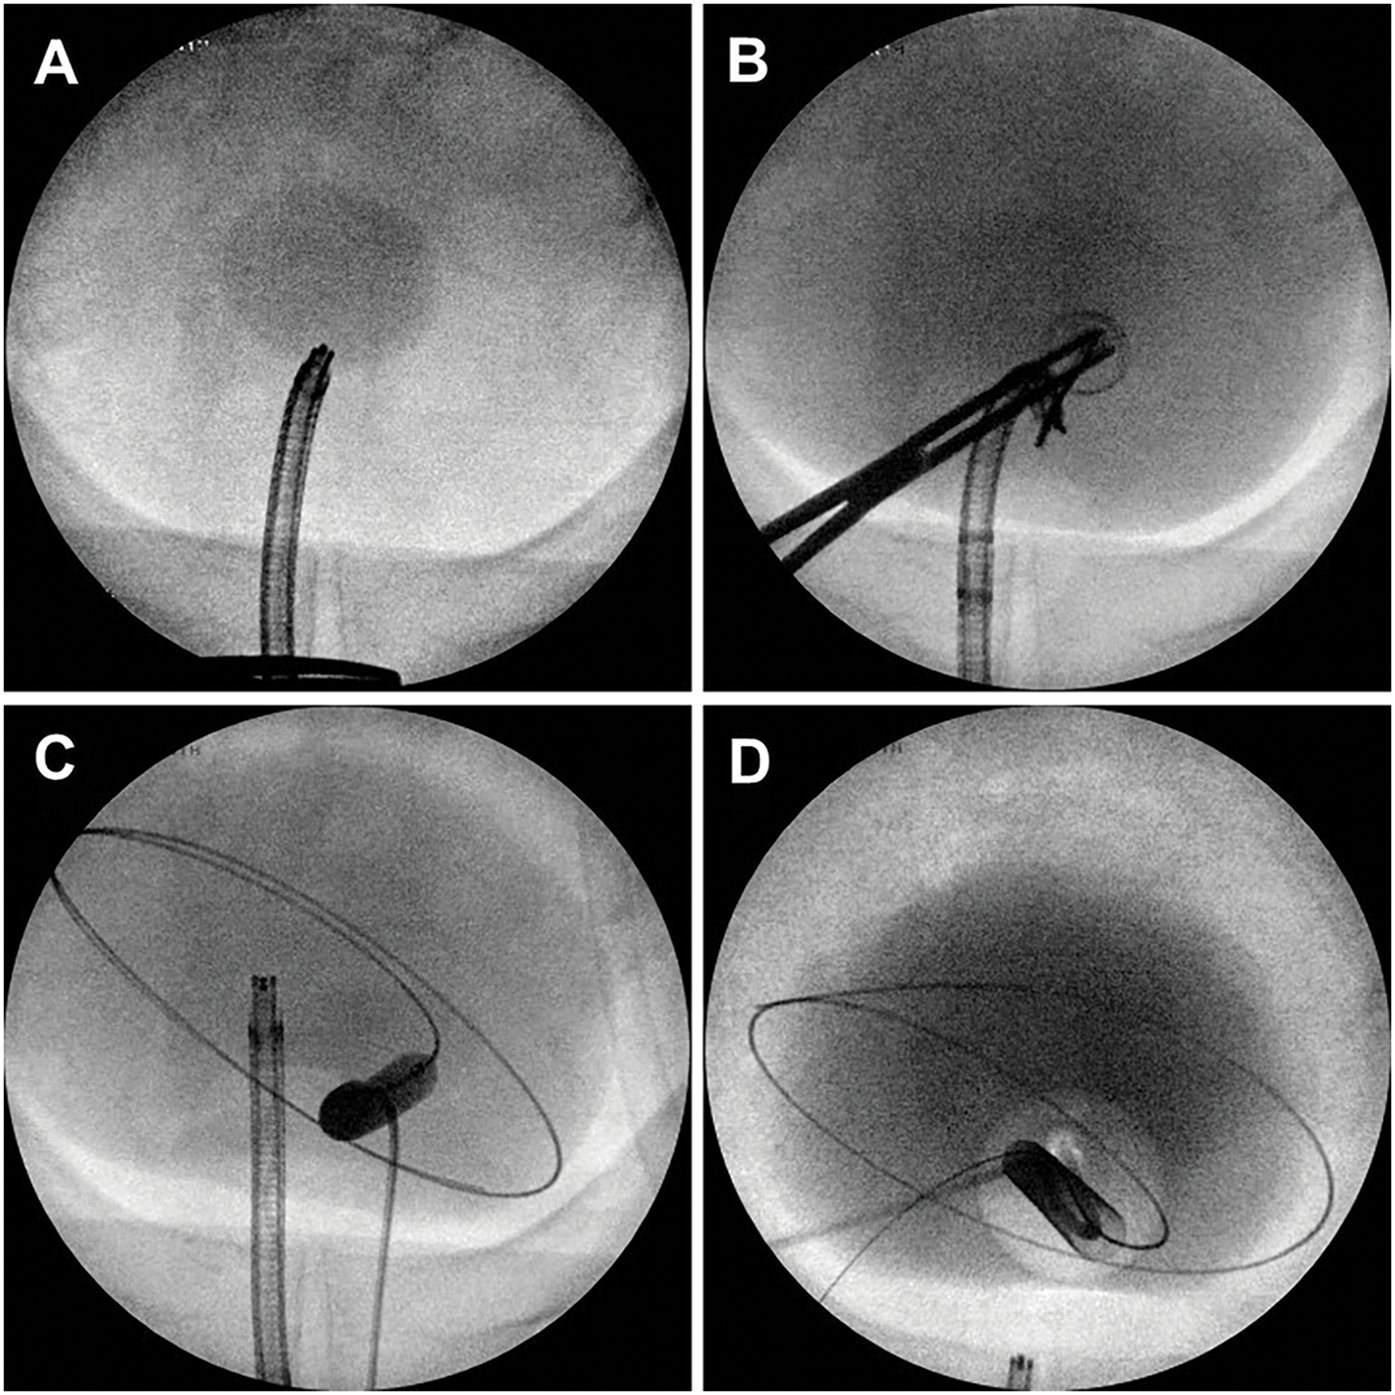

The technique for initial access mirrors percutaneous renal access. Scout fluoroscopy can confirm the stone position (Figure 1A). We perform the initial puncture using a percutaneous access needle (Boston Scientific NaviGuide™ Percutaneous Access Needle, 18 gauge). A bull’s eye technique facilitates a midline suprapubic puncture directly over the stone (Figure 1B). Successful bladder entry should yield urine return through the hollow needle. Two guidewires are passed and curled in the bladder. The safety wire is secured to the drape. If the access is performed under vision, needle entry and wire passage may be confirmed directly (Figure 2A). In patients with a pre-existing suprapubic tube (SPT), a guidewire may be directed through or alongside the catheter to obtain access. Performing a cystogram through the SPT may help confirm the wire position.

Figure 1: Intraoperative fluoroscopic cystography demonstrating (A) large bladder stone, (B) percutaneous needle access using bull’s eye technique, (C) balloon dilation of cystostomy tract, (D) final cystogram following suprapubic catheter placement

Once bladder access is achieved, the cystostomy tract is sequentially dilated. We typically pass an 8 Fr fascial dilator followed by a 24 Fr or 30 Fr dilation balloon (Boston Scientific NephroMax™ High-Pressure Balloon Catheter). The balloon is dilated with contrast so that it can be visualized under fluoroscopy during inflation (Figure 1C), and any “waisting” indicative of incomplete dilation is revealed. In patients with a chronic SPT, fascial fibrosis may preclude successful balloon dilation, and manual dilation with sequential Amplatz dilators may be required. Once complete dilation is achieved, an access sheath is advanced over the balloon into the bladder to establish the cystostomy tract. The balloon is deflated and removed, maintaining the safety wire outside the sheath. A rigid nephroscope with a parallel eyepiece is advanced into the bladder to confirm appropriate trajectory to the stones.

We perform a cystogram following stone treatment to rule out intraperitoneal extravasation (Figure 1D). There are several options for bladder drainage postoperatively. We generally leave a 14 Fr urethral Foley or a 16 Fr SPT for 5–7 days. However, no optimal duration or route of bladder catheterization has been established and thus may be directed by surgeon preference and patient anatomy.